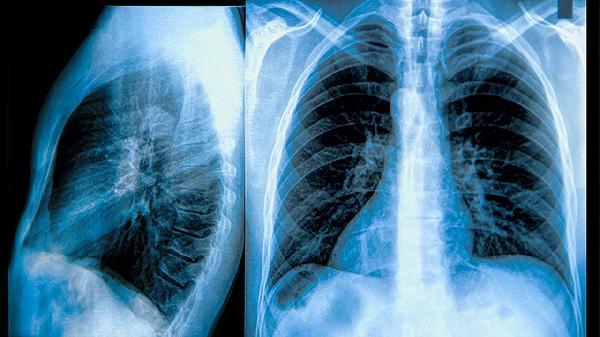

慢阻肺患者可在医生指导下使用布地奈德福莫特罗吸入粉雾剂、沙美特罗替卡松吸入粉雾剂、噻托溴铵粉吸入剂、氨茶碱片、乙酰半胱氨酸颗粒等药物缓解症状。慢阻肺是一种以持续气流受限为特征的慢性气道炎症性疾病,需长期规范治疗。

3、噻托溴铵粉吸入剂

噻托溴铵粉吸入剂是长效抗胆碱能药物,通过阻断M受体持续松弛支气管平滑肌,适用于慢阻肺的长期维持治疗。该药每日仅需吸入一次,但可能引发口干和排尿困难等抗胆碱能副作用。